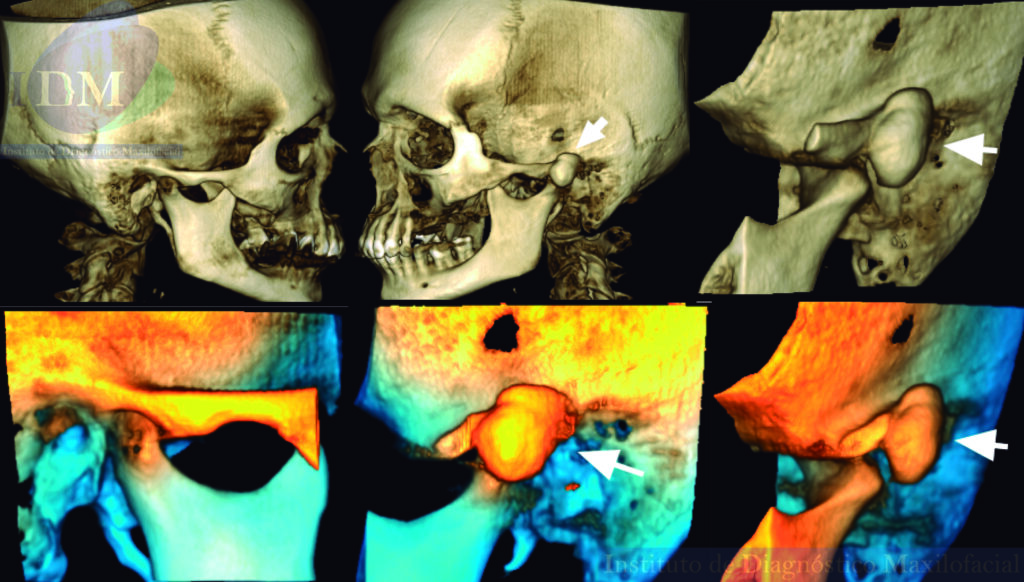

Al observar la tomografía volumétrica de haz cónico (en las reconstrucciones multiplanares, vistas transaxiales y tangenciales) se evidencia la misma imagen de forma redondeada y de densidad ósea que se localiza en la zona infratemporal y en la región posterior del arco cigomático izquierdo próximo a la cavidad glenoidea que a su vez estaría ocasionando un aplanamiento del contorno condilar en su cara externa.

RECONSTRUCCIÓN 3D